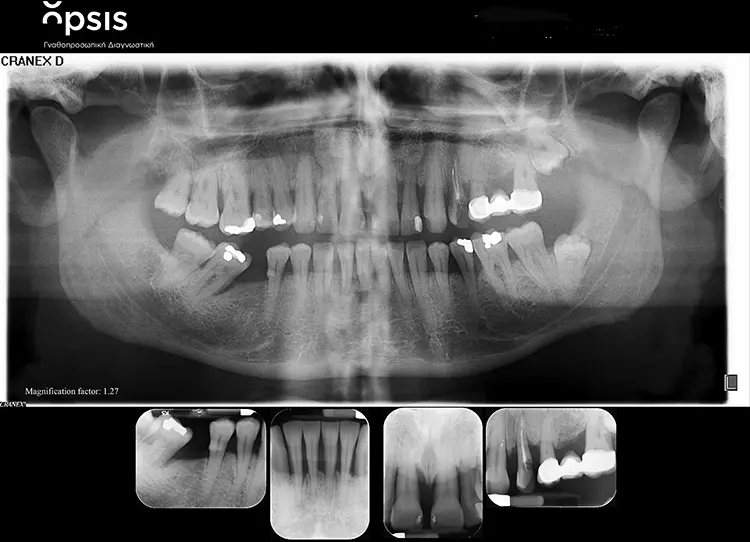

Die Restaurationen fügten sich sowohl klinisch als auch ästhetisch durch ihre spezielle Charakterisierung in die bestehende Patientensituation ein (Abb. 13-15). Auch röntgenologisch konnte eine gute Passform ermittelt werden (Abb. 16).

Der fehlende Zahn 24 wurde ebenfalls mittels eines Semados RS Implantats (BEGO Implant Systems GmbH & Co. KG) mit einer Länge/einem Durchmesser von 4,1/10,0 mm und einer monolithischen Zirkonoxidkrone ersetzt (3D Pro). Die klinische Situation konnte im Rahmen einer Nachuntersuchung im September 2022, fast zweieinhalb Jahre nach der Versorgung im Mai 2020 als sehr gut bezeichnet werden (Abb. 17-20).

Aus fachlicher Sicht konnte – trotz des Höhenverlusts im Papillenbereich – durch die Ridge Preservation nach Extraktion mittels Implantaten ein ausreichender horizontaler Kammerhalt erzielt werden. In wie weit sich die parodontale Vorerkrankung langfristig auf den Implantaterfolg auswirken wird, bleibt zum jetzigen Zeitpunkt abzuwarten. Erkenntnissen aus der Literatur zufolge ist das Risiko eines Implantatverlusts und der Entstehung einer Periimplantitis bzw. eines erhöhten krestalen Knochenverlusts bei Versorgung von Patienten mit einer parodontalen Vorerkrankung mit festsitzenden implantatprothetischen Versorgungen über einen Zeitraum von fünf bis zehn Jahren signifikant erhöht [23,24].

Eine intensive Nachsorge und die Versorgung nach dem Platform Shift-Konzept könnten im vorliegenden Patientenfall durchaus als protektive Faktoren in Frage kommen. Insbesondere bei Patienten mit einer Parodontitis kann das Risiko der Entstehung einer periimplantären Erkrankung effektiv gesenkt werden [25]. Krestale Knochenverluste hingegen können im kompromittierten Alveolarfortsatz mittels des Platform Shift-Konzepts der RS-Implantate signifikant im Vergleich zu einer Implantat-/Abutment-Kombination mit einem Platform Match-Design reduziert werden, wie eine aktuelle klinische Studie ergab [26].